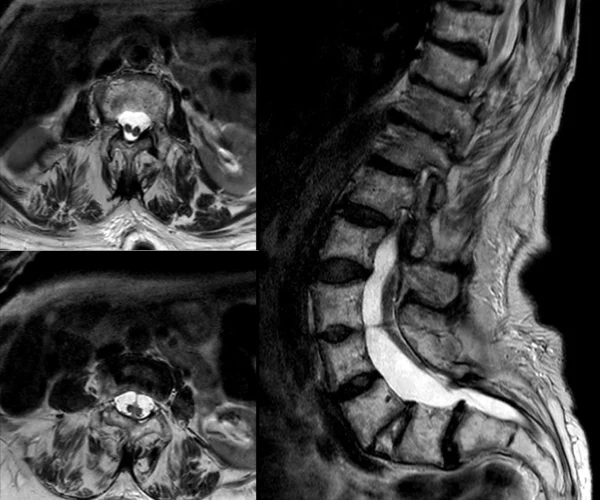

- Syringomyelia

- Chiari Malformation

- Tethered cord syndrome